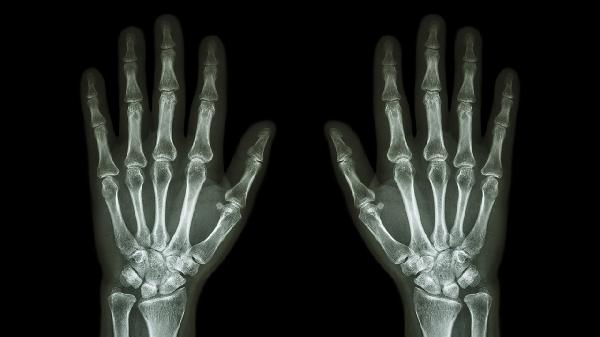

桂枝、细辛等温经药材对冬季加重的老寒腿效果显著,能改善末梢血运障碍导致的手足麻木。使用时需配合热敷促进药物渗透,但糖尿病患者及皮肤敏感者应慎用,防止低温烫伤或接触性皮炎。